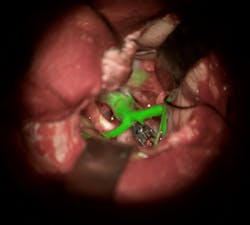

Leica Microsystems (Buffalo Grove, IL) has received U.S. FDA approval to market its augmented reality (AR) GLOW800 surgical fluorescence for vascular neurosurgery. In combination with the indocyanine green (ICG) fluorescent dye, GLOW800 allows surgeons to observe cerebral anatomy in natural color, augmented by real-time vascular flow in a single image, with full depth perception. This AR solution provides the surgeon a complete view of anatomy and physiology to support crucial decisions and actions during vascular neurosurgery.

GLOW800 AR fluorescence is the first of many imaging modalities that will be based on the GLOW AR platform from Leica Microsystems. GLOW AR modalities can be fully integrated in the ARveo digital AR microscope, which launched earlier in 2018. Following the U.S. FDA clearance of GLOW800, ARveo customers in the U.S. can experience the full advantages of AR visualization in the operating room.